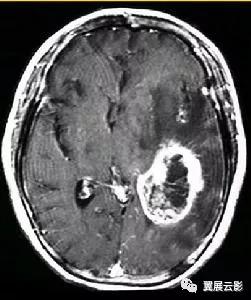

病例1:多发脑转移瘤

MR平扫转移瘤多呈等T1或长T1,等T2或长T2信号,瘤体内囊变坏死区呈明显长T1长T2信号,个别具有顺磁效应的转移瘤如黑色素瘤可出现短T1短T2信号,增强扫描病灶一般呈结节状或环状强化,转移瘤周围常有显著的脑水肿。多发脑转移瘤重点强调病变的位置发生在大脑,小脑,还是其他部位,病灶具体位于哪个脑叶,病灶是否位于皮,髓质交界区,病灶的形态和数目,平扫T1WI,T2WI信号特点及增强扫描所见,应密切观察瘤体内是否合并坏死,囊变等合并征象,本病需要与多发性脑脓肿,脑囊虫等疾病相鉴别,结合病史和原发肿瘤情况一般鉴别诊断不难。

病例2:单发脑转移瘤

单发脑转移瘤在报告书写时重点强调病灶的位置,形态,大小,平扫T1WI及T2WI信号特点及增强扫描时所见,重点要与胶质瘤,脑膜瘤和脑脓肿做鉴别。